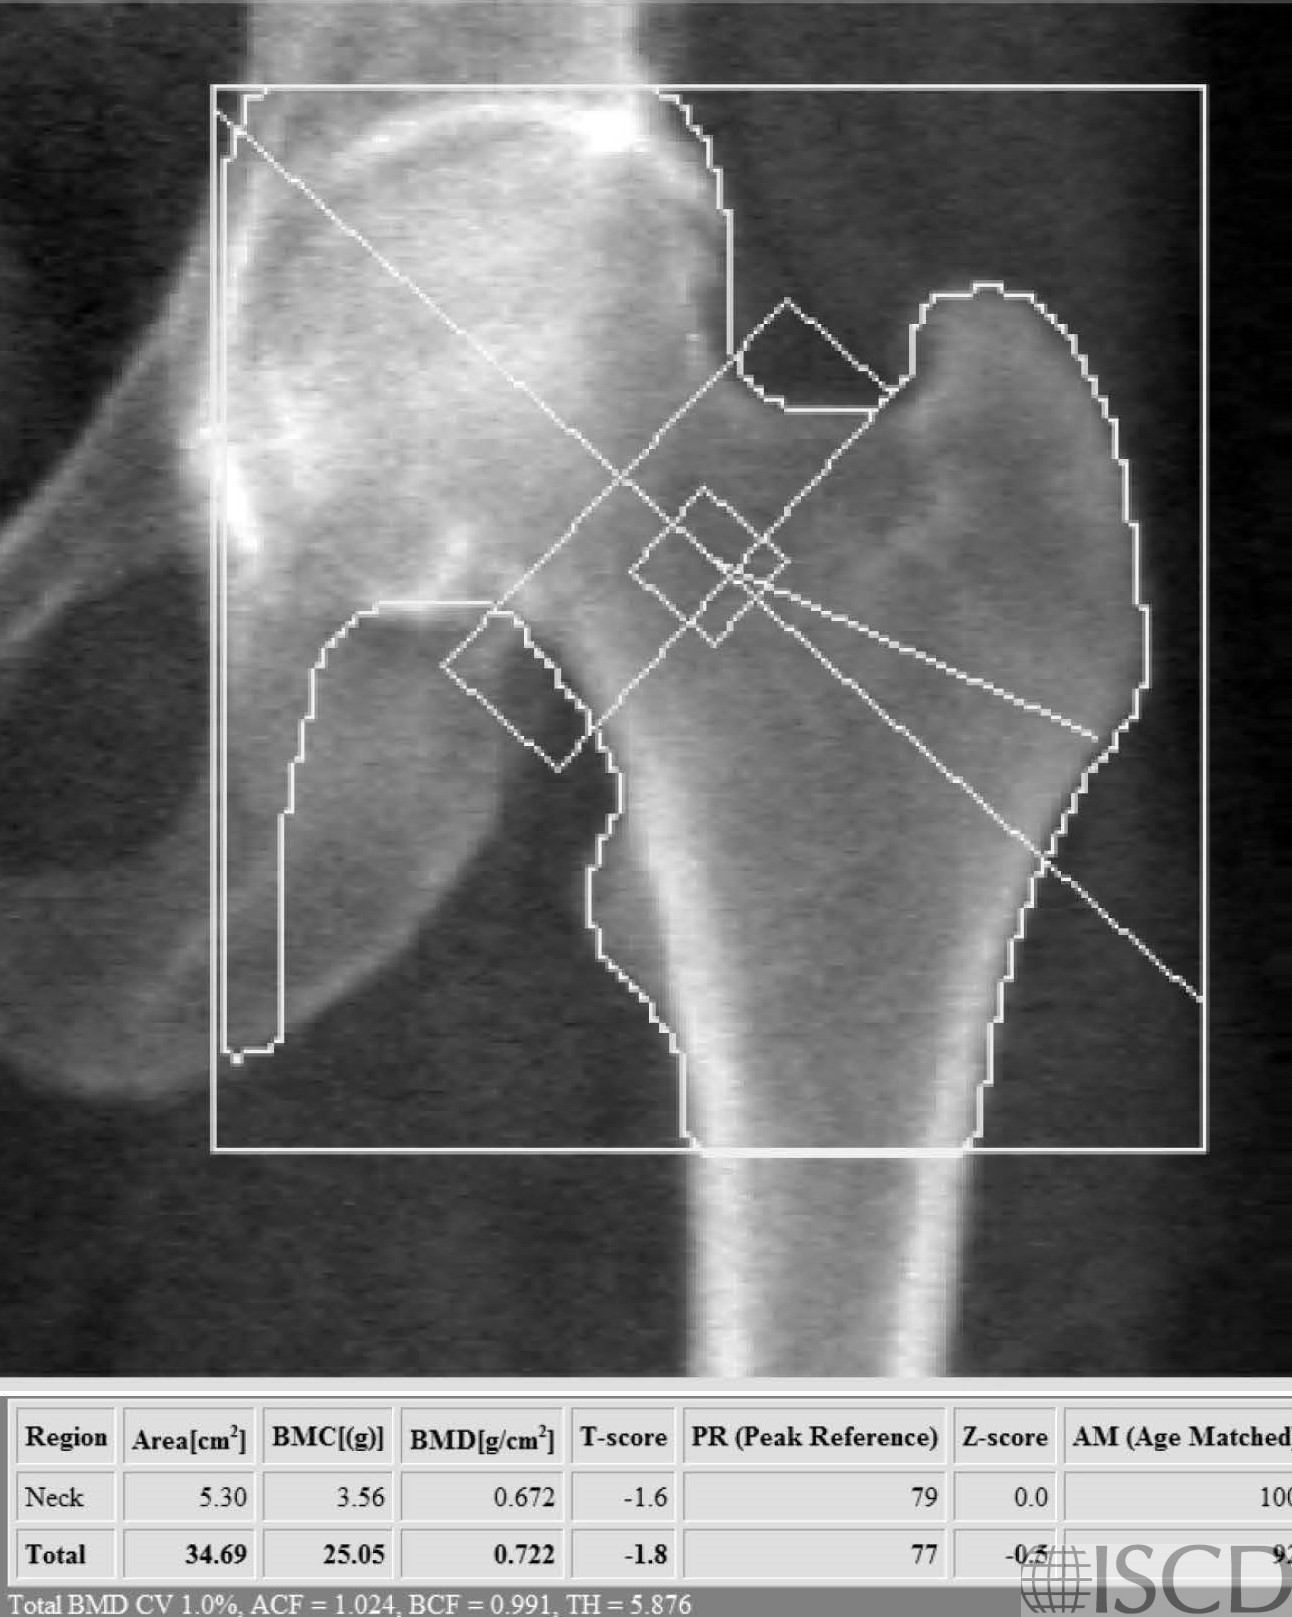

This is the left proximal femur Hologic scan from the same patient with hypermobile Ehlers-Danlos syndrome.

This is a DXA scan from a patient with hypermobile Ehlers-Danlos syndrome. The thoracic and lumbar spine radiographs showed demineralization and no other abnormalities. Bone mineral density can be variable in Ehlers-Danlos syndrome. Low bone mass is found in kyphoscoliotic, arthorchalasia (congenital hip dislocation, generalized joint hypermobility with recurrent joint dislocations), spondylodysplastic, and classic Ehlers-Danlos. In hypermobile and classic Ehlers-Danlos there are reports of mildly decreased bone density, but fracture risk may not always be increased.